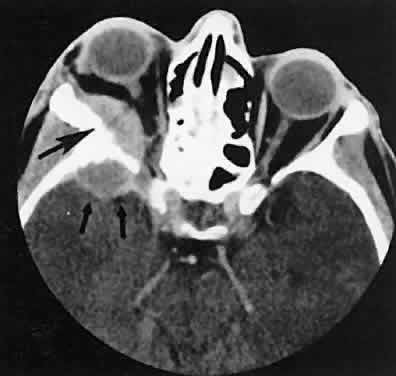

The muscle belly has a smooth contour with no edema of the adjacent orbital fat. We recently evaluated a patient with a referral diagnosis of Graves' orbitopathy. The patient was euthyroid but had severe orbital congestion typical of advanced Graves' orbitopathy. Imaging showed “dirty” orbital fat and lateral rectus muscle morphology that seemed atypical (Fig. 8). Biopsy specimen results showed a low-grade lymphoma. Hypertrophy of the medial rectus muscle can cause the medial wall to bow in toward the ethmoidal sinus from the chronic effects of pressure on the bone. The hypertrophied muscles also can give rise to a compressive optic neuropathy in the orbital apex as the enlarged muscles take their origin from the anulus of Zinn. Axial views of the apex show an apparent mass if the inferior rectus muscle is enlarged. It is imperative that additional views, sagittal or preferably coronal, be obtained to show the true nature of this apparent mass. Intracranial fat prolapse, seen by CT, may be another sign of optic neuropathy.44 An optic neuropathy also can be seen with relatively normal-sized EOM. An expanded fat compartment with optic nerve stretch has been associated with an optic neuropathy.45,46

Fig. 8. Low-grade lymphoma confined to orbit mistaken for Graves' ophthalmopathy in a 65-year-old man. A. On the axial view, orbital fat appears “dirty” with marked increase in soft tissue stranding. Muscles do not have a smooth appearance, lateral rectus muscles have lumpy appearance (arrow), and both lateral rectus muscles are disproportionately large for what typically is seen in Graves' orbitopathy. B. Coronal view also shows dirty orbital fat. Note left inferior rectus, which is small (arrowhead), and also is atypical in Graves' orbitopathy when there is enlargement of the other extraocular muscles.